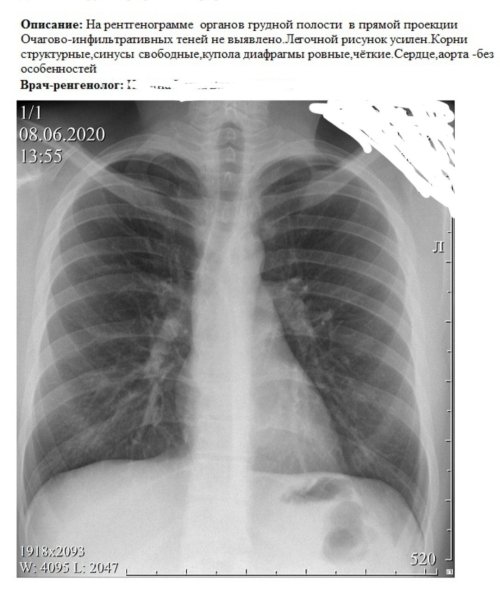

Усиление сосудистого рисунка легких у ребенка может быть признаком различных патологий и состояний. Это визуальное изменение на рентгеновских снимках обычно связано с увеличением притока крови в сосуды легких, что может указывать на наличие воспалительных процессов, инфекций или аллергических реакций. Также это наблюдается при повышении давления в легочной артерии, что может быть вызвано сердечными заболеваниями или другими патологиями системы кровообращения. В любом случае, обнаружение усиленного сосудистого рисунка легких у ребенка требует дополнительного обследования и консультации с педиатром или пульмонологом для постановки точного диагноза и назначения соответствующего лечения.